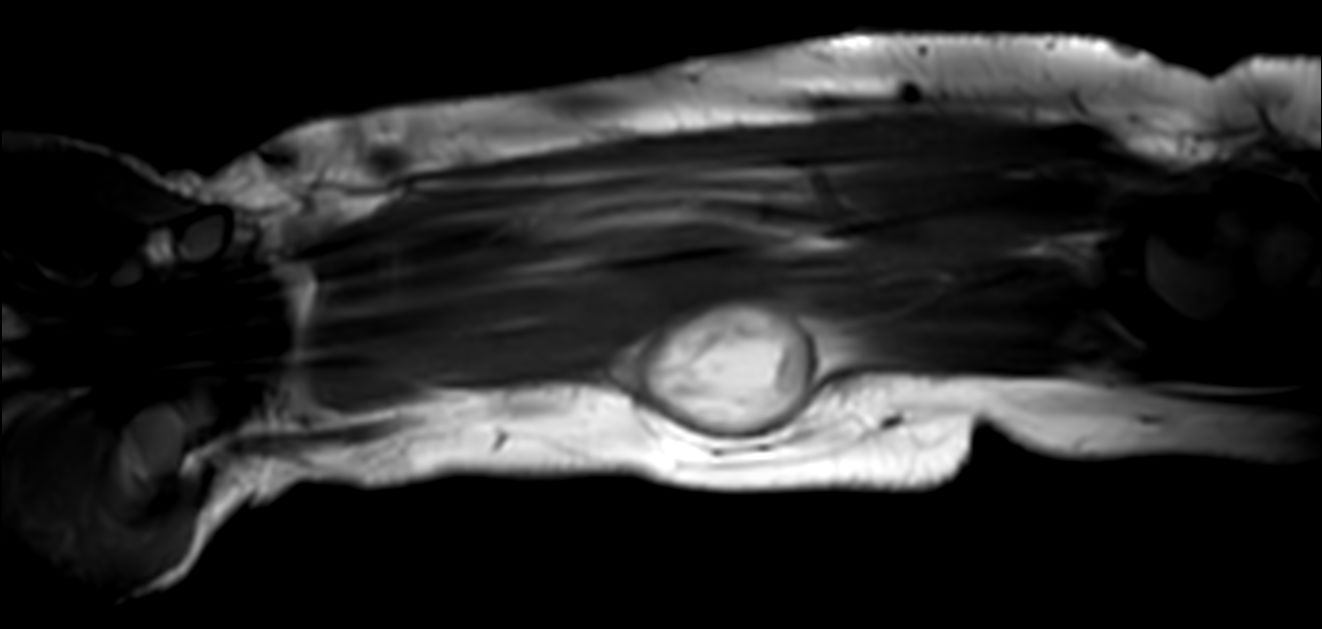

Pediatric forearm with lesion

Pediatric patient with a lesion in the forearm. mDIXON XD provides uniform fat-free imaging and allows for multiple image types in one single scan. Integration of Compressed SENSE acceleration technique enables speeding up of the entire exam.

Coronal T1w TSECompressed SENSE

Sagittal T1w TSECompressed SENSE